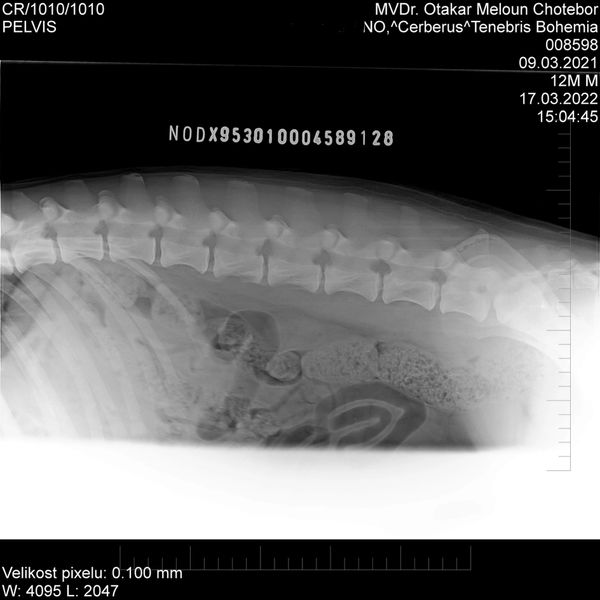

HD: A

Spondy: Free